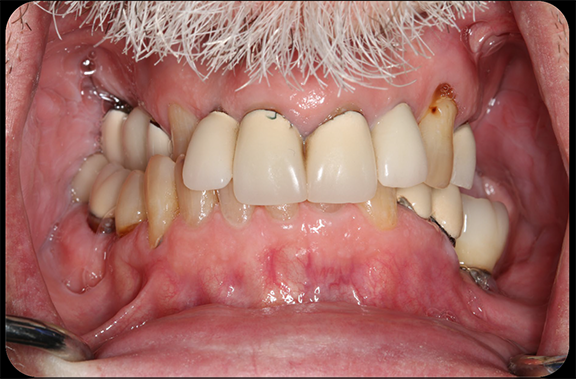

In a more complicated case, often there are more complicated starting points. The patient shown in Figure 8 had bite posture problems, caries, periodontal disease, failing restorations and implants, and a history of head-and-neck cancer. Such a patient may logically fear the unknowns of treatment, but with the treatment planning and rendering capabilities robotics provide, the practitioner could determine exactly what the patient needed, convey the information to the patient, and deliver promised results.

Fig 8. The patient had bite posture problems, caries, periodontal disease, failing restorations and implants, and a history of head-and-neck cancer.